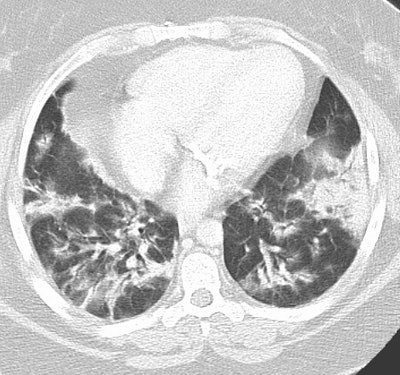

Cryptogenic Organizing Pneumonia (BOOP):

The patient shown below had a long history of inflammatory bowel disease for which she was receiving treatment with sulfasalazine. This agent can result in BOOP.

The CT scan demonstrates subpleural, patchy consolidations with air bronchograms. Patchy areas of ground-glass are also seen. Peribronchial thickening as shown in this case is a common finding.